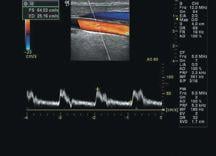

Vascular Ultrasound Boasts Portability

Recognized as the least costly option for vascular imaging, vascular ultrasound is common, and very effective at imaging vessels close to the skin surface. It is also noninvasive like CTA and MRA, but with ultrasound, there is no contrast material used and no radiation dose is administered. Ultrasound images are captured in real time, so radiologists can see the blood flow to organs and tissue in the body. Another notable benefit is the ability to do the procedure at a patient’s bedside. This can be significant if a patient is unable to be moved into a vascular lab for a CT or MR study.

Despite the fact that vascular ultrasound is very patient friendly, there are some deficiencies. Operator dependence is viewed by some as a problem. The dispute lies in the amount of time needed to train an individual on ultrasound. It takes longer to train to use ultrasound than a CTA or MRA, and the same results can often be viewed in much less time. Vascular ultrasound also has problems imaging vessels deep in the body, which can affect viewing vessels in bariatric patients.